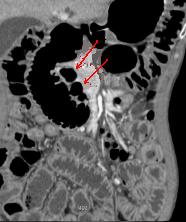

Ulcer de la face posterieure duodenum

perfore . Image de bulbe d'air extravation

exterieure justalesionelle ( fleche blanche )

. Image TDM en coupe axiale . |